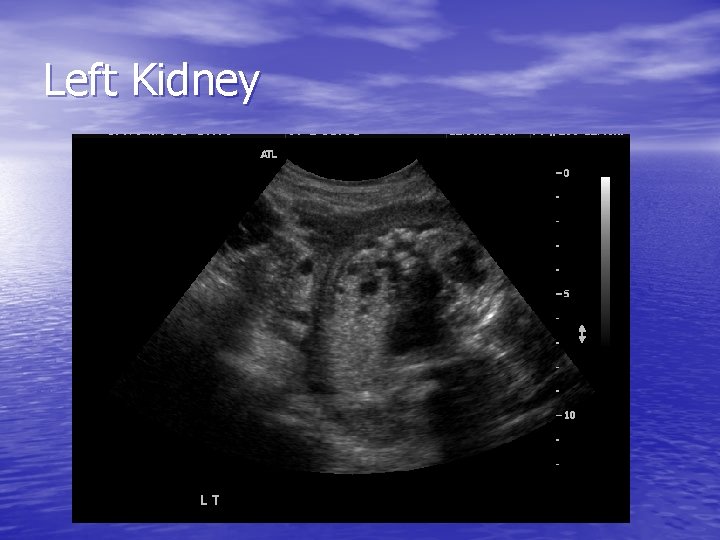

Left Kidney

WU – ultrasound cont • Long axis of the kidney is measured when evaluating underlying hydronephrosis • Kidneys which are large for gestational age and are less hyperechogenic – better prognosis • Kidneys which are hyperechogenic and are small have poorer prognosis due to advanced renal fibrosis